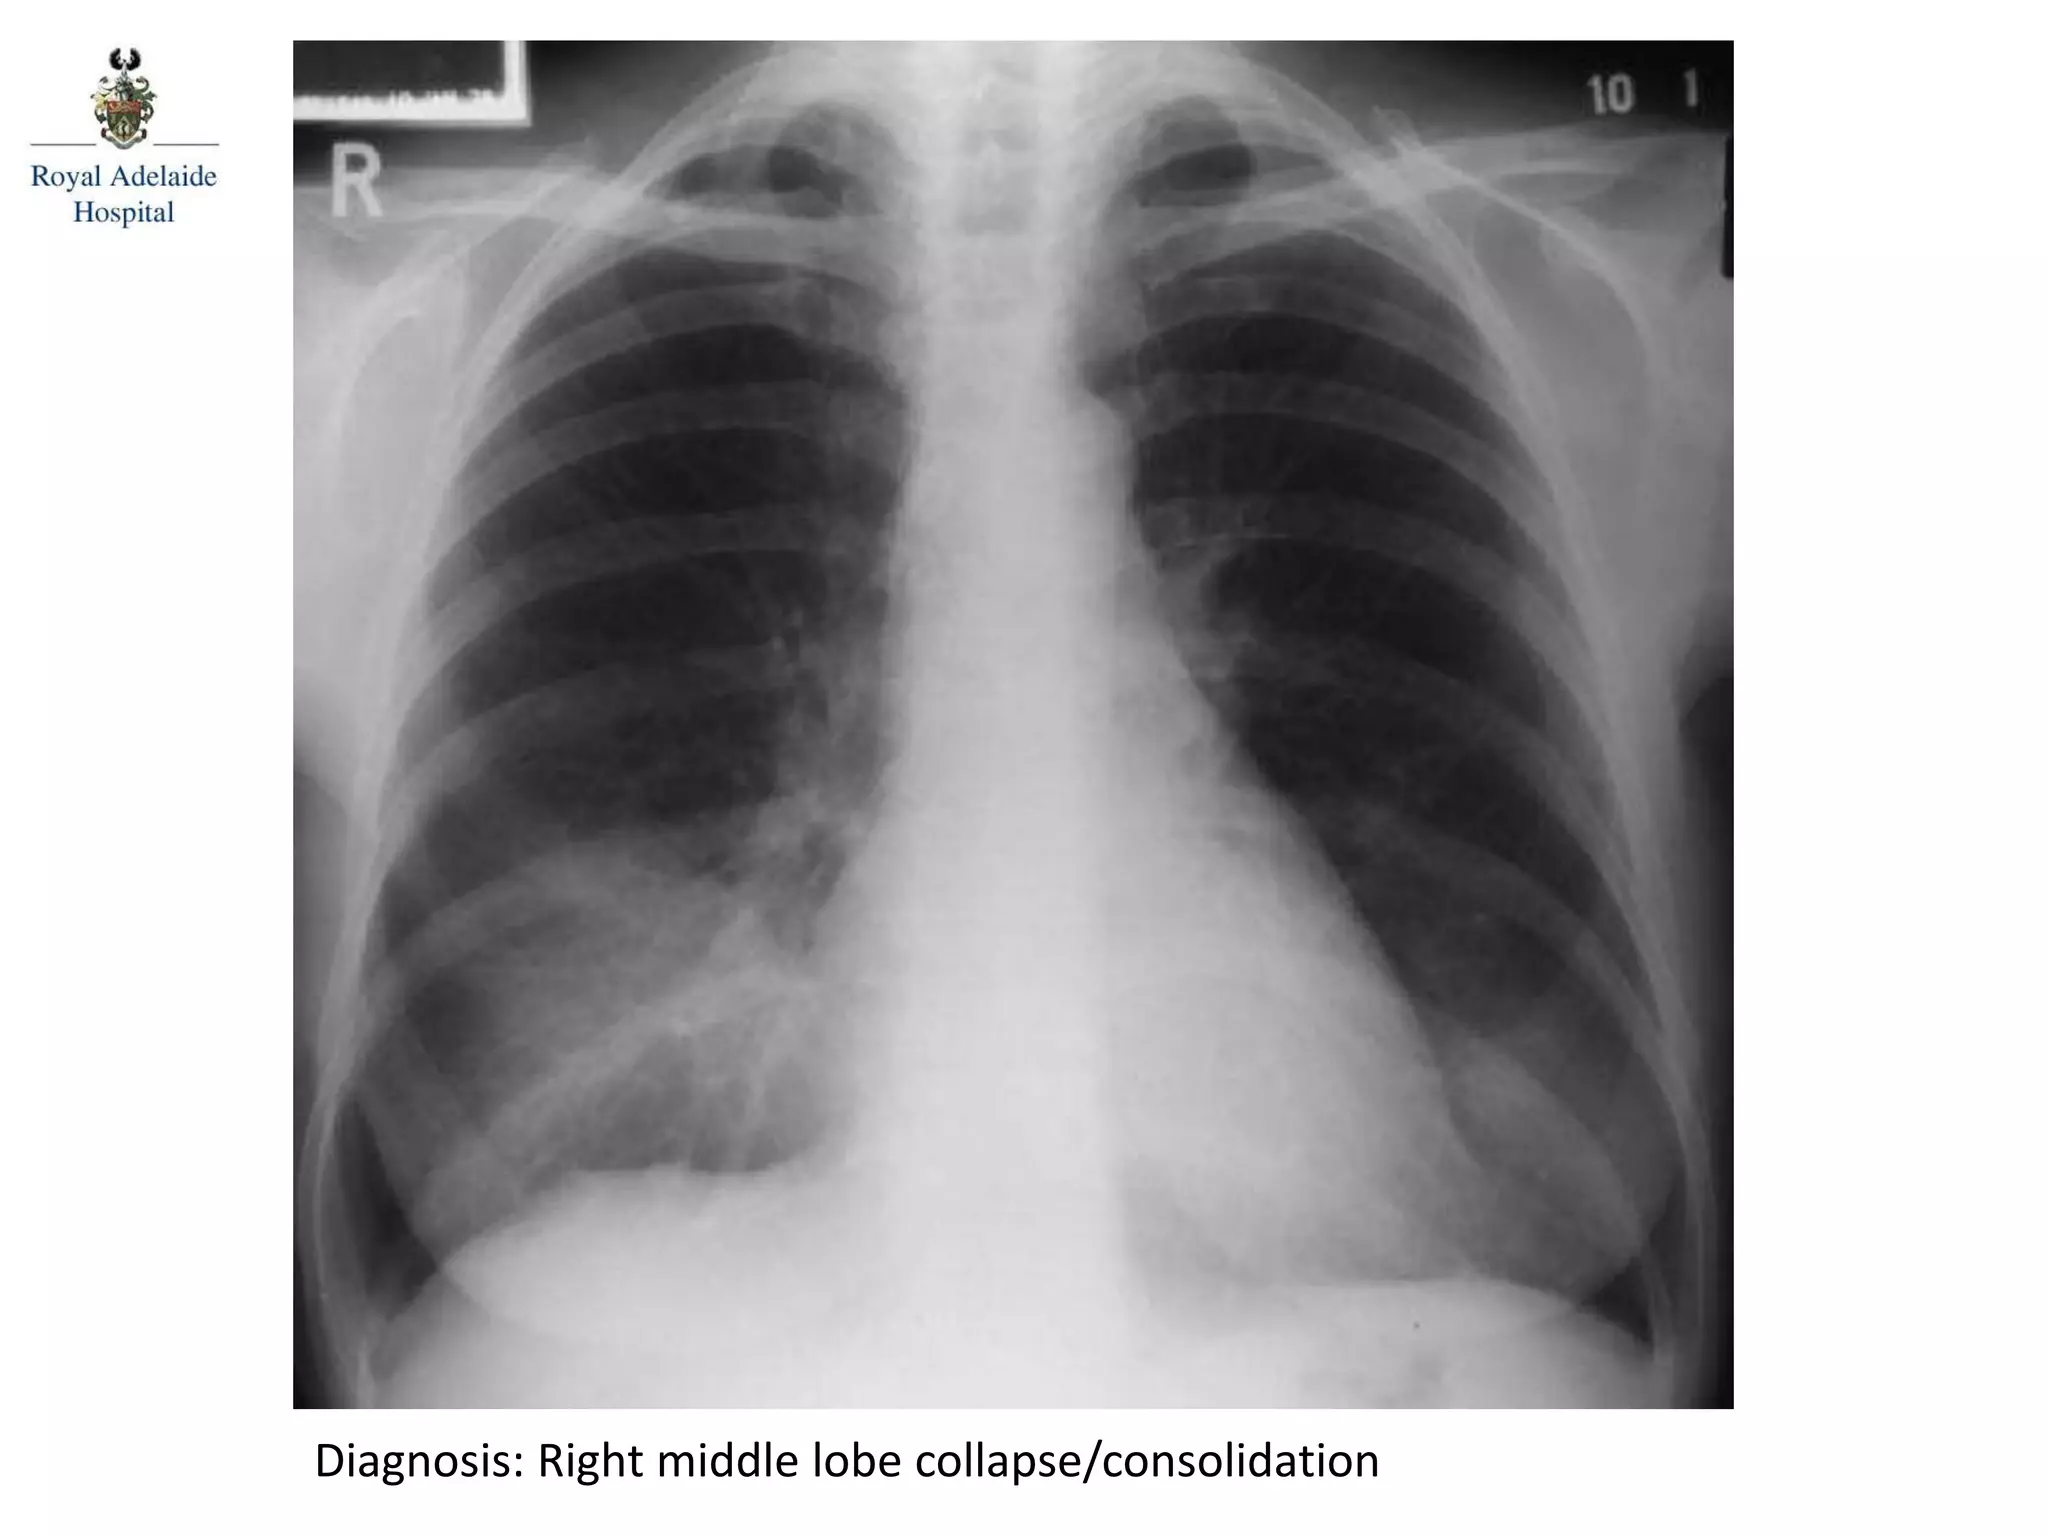

Diagnosis: Right middle lobe collapse/consolidation